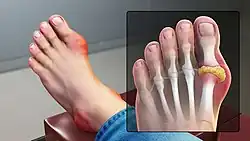

Gout can present in multiple ways, although the most common is a recurrent attack of acute inflammatory arthritis (a red, tender, hot, swollen joint).[7] The metatarsal-phalangeal joint at the base of the big toe is affected most often, accounting for half of cases.[10] Other joints, such as the heels, knees, wrists, and fingers, may also be affected.[7] Joint pain usually begins during the night and peaks within 24 hours of onset.[7] This is mainly due to lower body temperature.[4] Other symptoms may rarely occur along with the joint pain, including fatigue and a fever.[10][15]

Gout presenting as slight redness in the metatarsal–phalangeal joint of the big toe